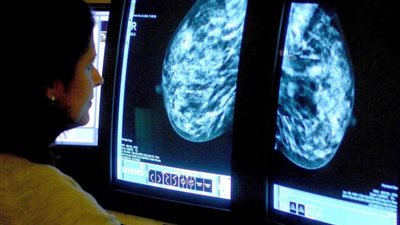

كشفت دراسة طبية حديثة النقاب عن أن سرطان الرئة يعد الأكثر فتكا بين البريطانيات، متفوقا على سرطان الثدى بمعدلات ملحوظة. وتشير البيانات إلى أن سرطان الرئة يفتك بأكثر من 16 ألف سيدة بريطانية سنويا، وذلك ...

نشر الموقع الإسبانى "برينسا إيسكريتا"، اليوم الأحد، دراسة عن سرطان الرئة الذى يتسبَّب فى زيادة معدل وفيات السيدات أكثر من سرطان الثدى. وقد أجرى الدراسة باحثون من إيطاليا وسويسرا، والتى أفادت بأنه فى ...

أظهرت أحدث الأبحاث الطبية، أن وقوع الكثيرين فريسة لضغوط العمل والتوتر لا تزيد بينهم فرص الاصابة بالسرطان، خاصة سرطان الرئة والثدى والمستقيم أوالبروستاتا. وأكد الباحثون فى معرض أبحاثهم أن قرابة 90% ...